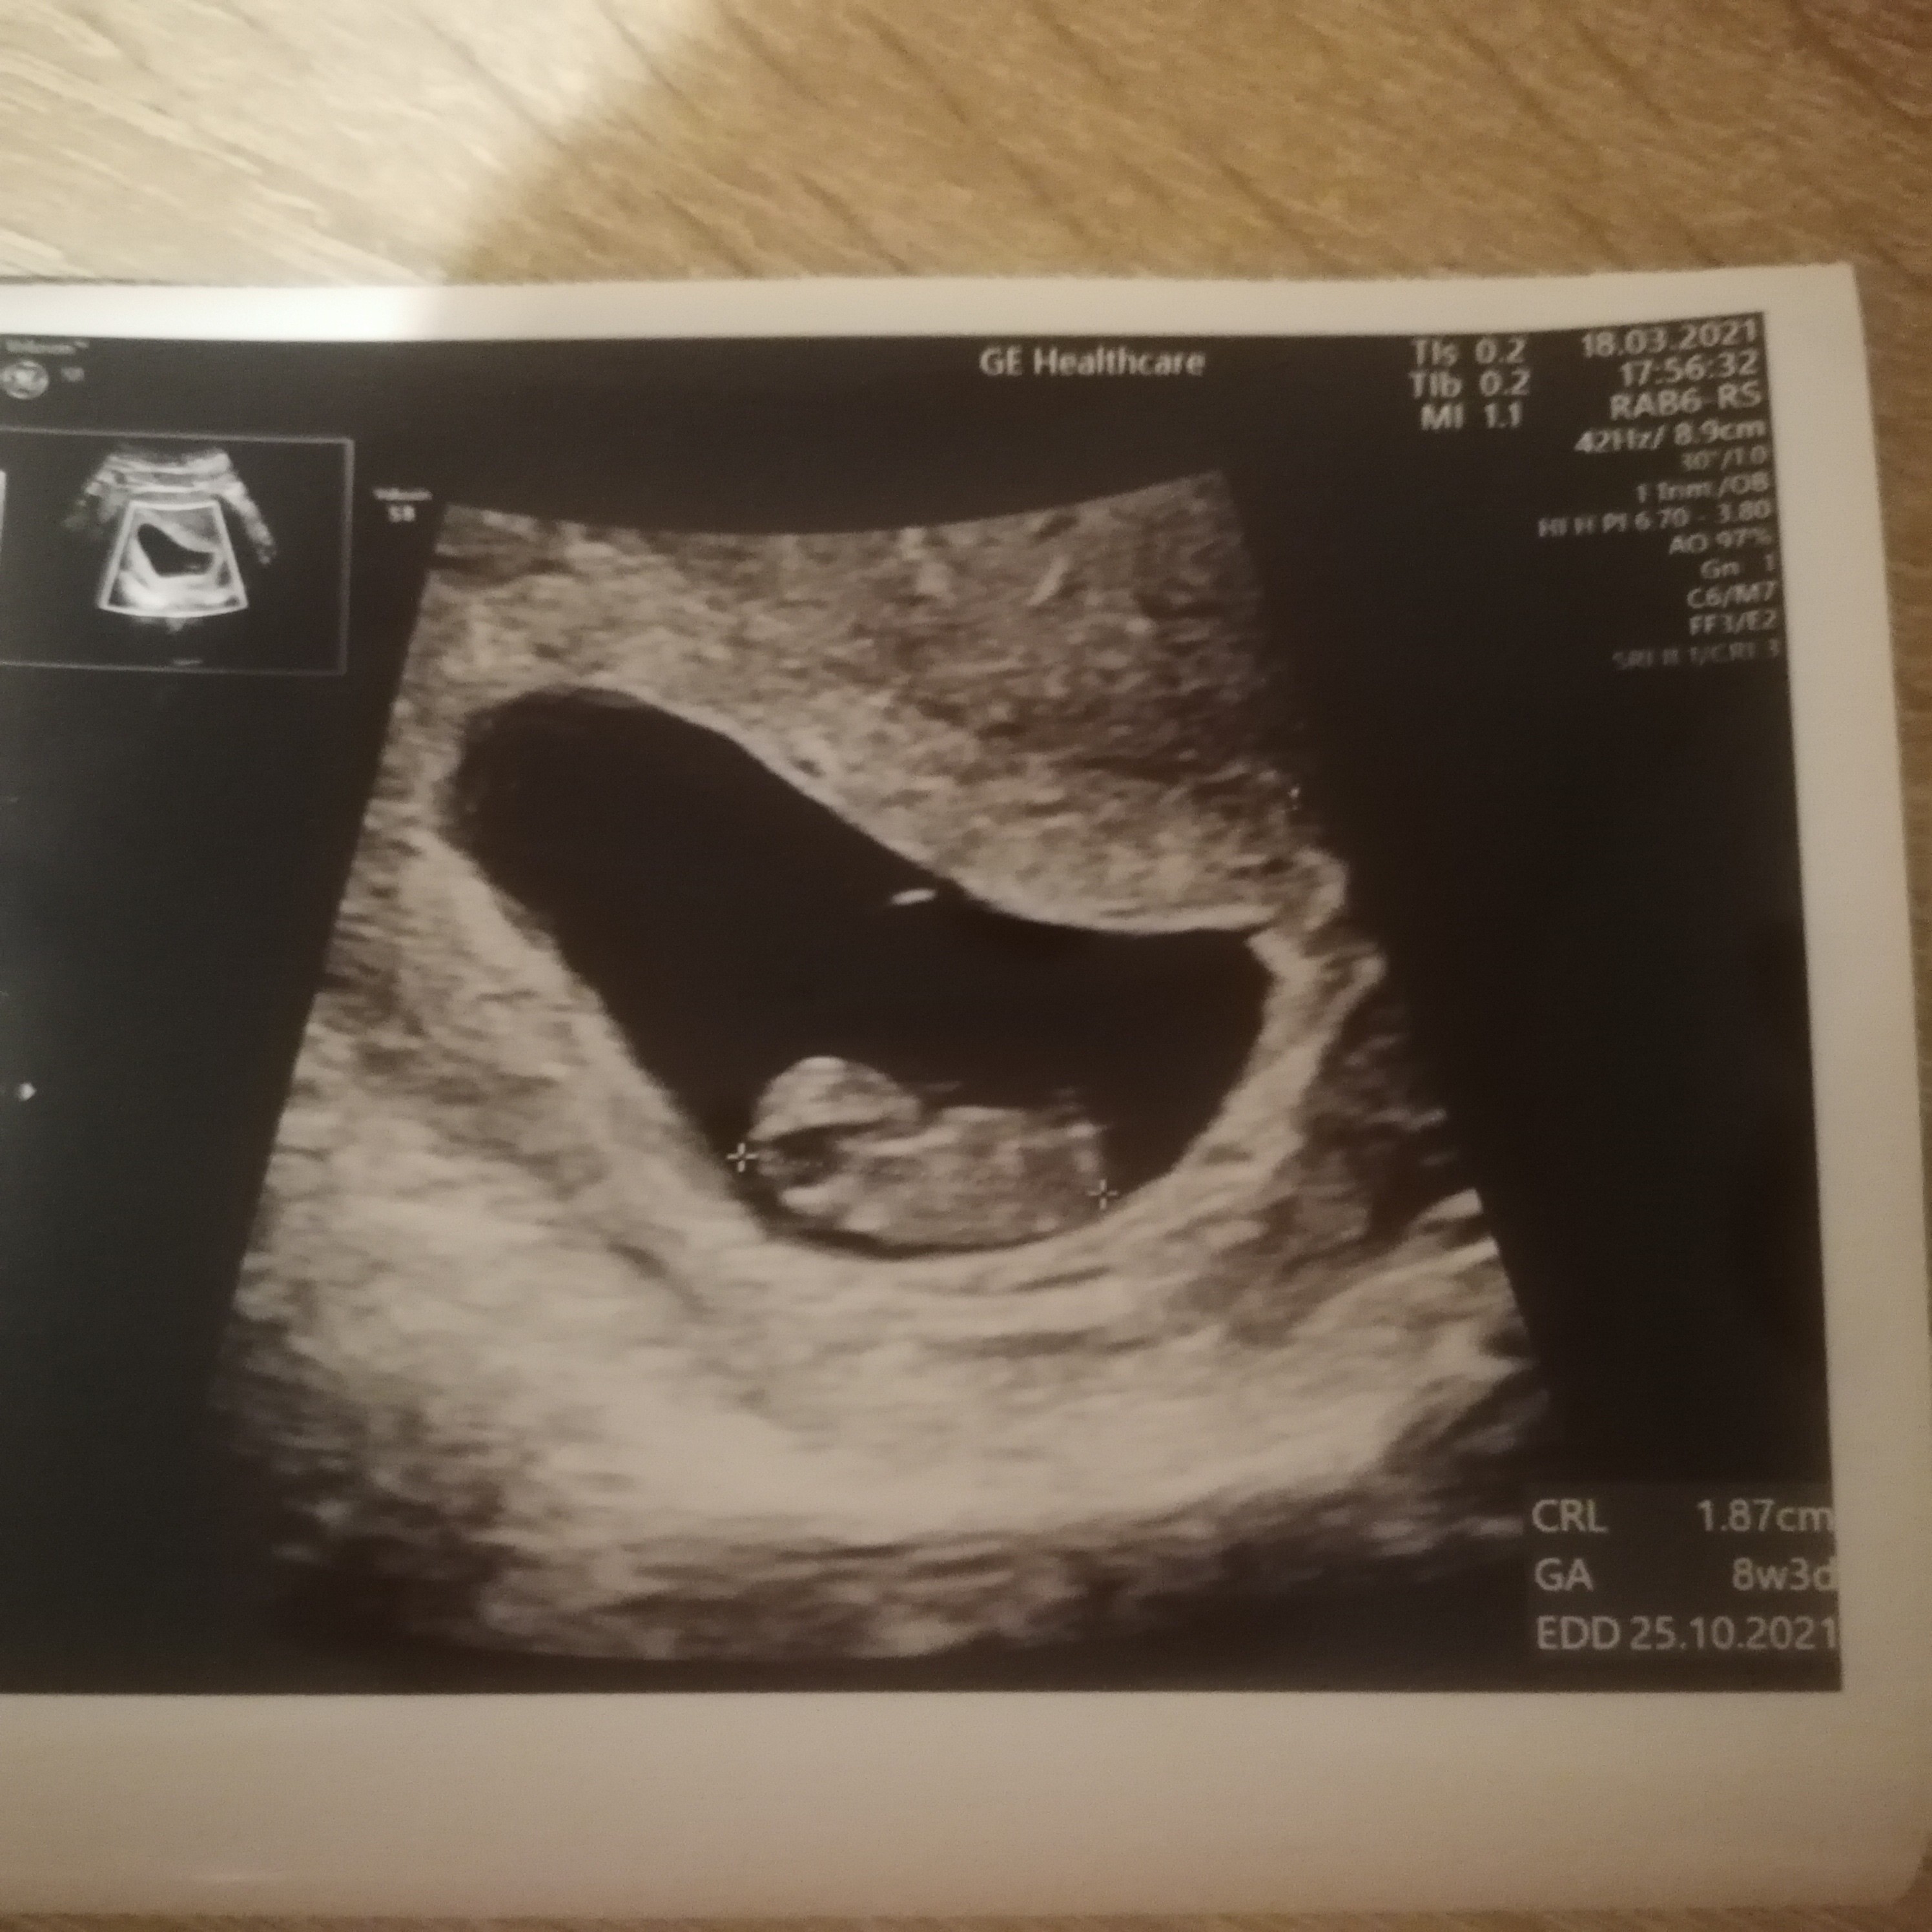

A maluszek rośnie na heparynie jak na drożdżach ❤️😍ma już 1.87cm i wskazuję to na 8t3d 😍temin na 25.10. Serduszko bije 😍to najważniejsze. Następna wizyta 1 kwietnia. Miałam szybką wizytę dzisiaj lekarz dla pewności chciał wyniki zobaczyć i jak ma się maluszek. Powiedział że wszystko rozwija się pieknie 😍

• IMG_20210318_181745.jpg

1,1 MB · Wyświetleń: 60